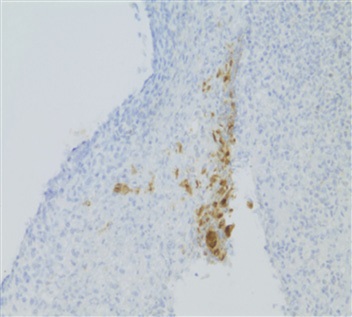

A 45-year-old female presented to our emergency department with severe, acute onset headaches. Her workup revealed lytic lesions in the calvarium and diffuse FDG avid lymphadenopathy (figure 1). Subsequent workup including biopsies of right inguinal, mediastinal and right axillary lymph nodes, and bone marrow, failed to demonstrate any etiology.

Figure 1: